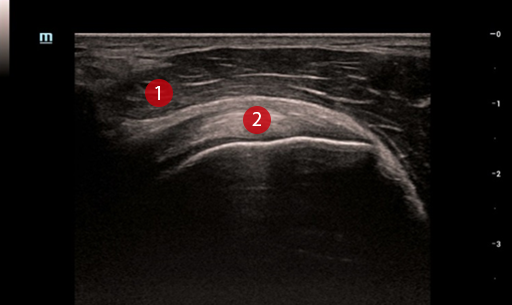

Новый алгоритм iClear+ устраняет спекл-шум и улучшает соотношение сигнал/шум, что делает картинку чище и контрастнее. Технология особенно полезна при работе с линейными датчиками и при исследовании молочных желёз. Resona R9 обеспечивает качественную визуализацию без артефактов, позволяет лучше различать структуру мышц и сухожильных волокон и получать детальную информацию о мягких тканях.

Плечевой сустав в режиме iClear+